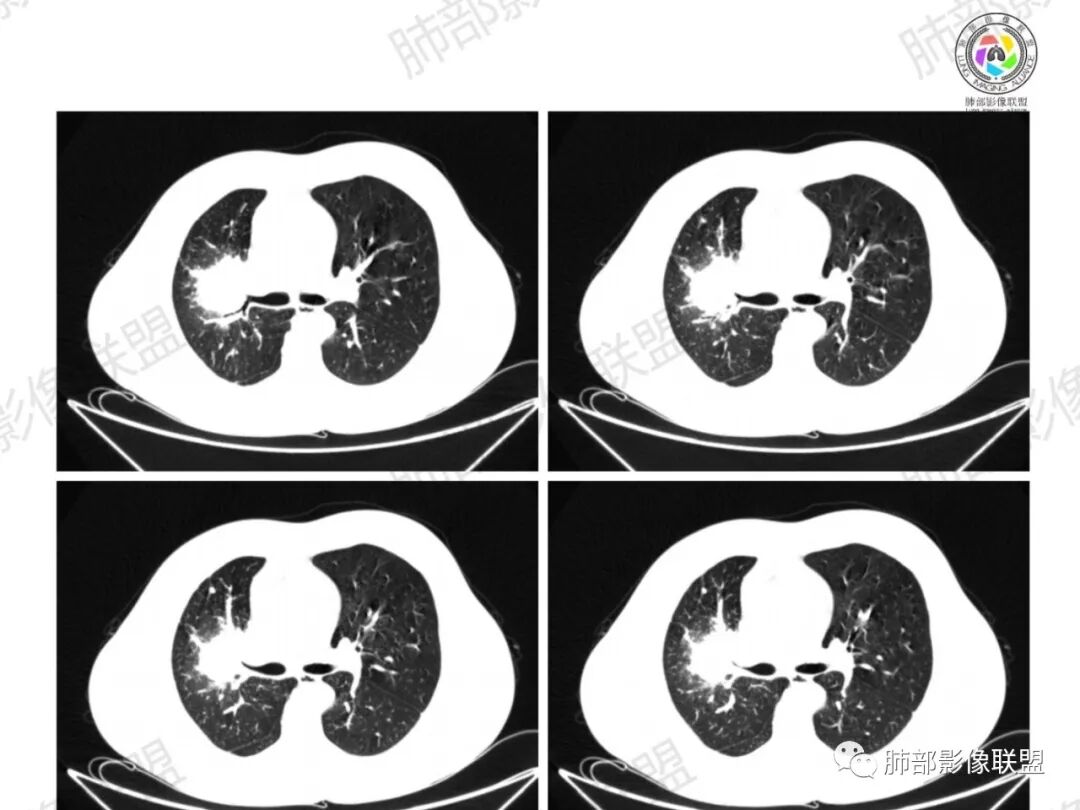

了:中年男性,右肺门肿块影,浅分叶,周围晕征,边缘清楚,小叶间隔增厚,树芽征,支气管截断,不均匀强化,内可见低密度坏死,纵隔淋巴结肿大,综合考虑肺部肿瘤并阻塞性肺炎

一切∮随缘:右肺门肿块影形态不规则,边缘毛糙,右肺上叶支气管堵塞,病变跨叶生长,远端血管束增粗,周围散在多发结节,部分位于胸膜下,平扫密度尚均匀,增强后不均匀强化,呈中度强化,坏死区无强化,纵隔淋巴结肿大。临床无感染症状,考虑恶性,鳞癌,腺癌,鉴别慢性脓肿。

那个人:中年男性,右肺肿块影,支气管截断,截断口非圆盾,病灶膨隆分叶,坏死,强化。病灶内血管破坏。病灶远端树芽及小结节影,考虑恶性,鉴别结核

周太狼:中年男性,吸烟史,陈旧结核史,呼吸道症状未提及,抗感染治疗无效。影像见右上肺门区软组织肿块影,浅分叶、毛刺,支气管似有截断,其内密度不均匀,不均匀强化,内可见低密度坏死区,病壮周围见斑片、结节影。纵隔内淋巴结稍肿大,首先考虑恶性,肺部肿瘤并阻塞性肺炎,肺鳞癌可能,鉴别结核。

弹指之间:中年男性,结核史、吸烟;右肺门肿块,特点:右肺上叶尖、前段支气管狭窄、部分阻塞(肿块大、支气管狭窄闭塞相对轻),肿块内血管部分残留(生长速度快,浸润>破坏),周围见渗出、炎症,部分实变;内见坏死、位于边缘区域;纵隔淋巴结肿大;考虑恶性,1.非支气管粘膜起源首先考虑,淋巴瘤?(但坏死相对多了);2.鳞癌(支气管阻塞轻);3.小细胞待排。

Coke with ice:病变整体收缩平直,毛刺较软,支气管壁增厚。支气管鼠尾状狭窄,于病灶以远可见显示。支气管粘液栓。相邻支气管血管推移明显,磨玻璃边缘模糊,多灶坏死边缘清晰,一部分血管自然穿行,猜个炎性病变。

这个比较大的坏死灶,边缘清晰,看似符合鳞癌坏死。仔细看看这个坏死边界,是血管阻挡引起的边界清晰。其他的病灶内低密度是柱形粘液栓。实性部分强化有轻度延迟强化。病变背景是双上肺的小叶中心结节。病变区的支气管壁是厚的。

妞妞:右肺门区病灶,边缘有GGO,模糊,远端树芽,支气管受阻,有圆钝感,病灶坏死,边缘清楚,实性成分有强化,不像鳞癌强化,首先考虑结核,鳞癌待排,建议支气管镜

良孑:右肺门肿块,有平直,u型凹陷及尖角征,远端可见散发树芽征,有支气管截断,肿块内坏死边界清,似可见围绕坏死的环状强化,综合分析首选炎性病变,TB可能,冇吸烟史,良恶性征象都有鳞癌要鉴别,